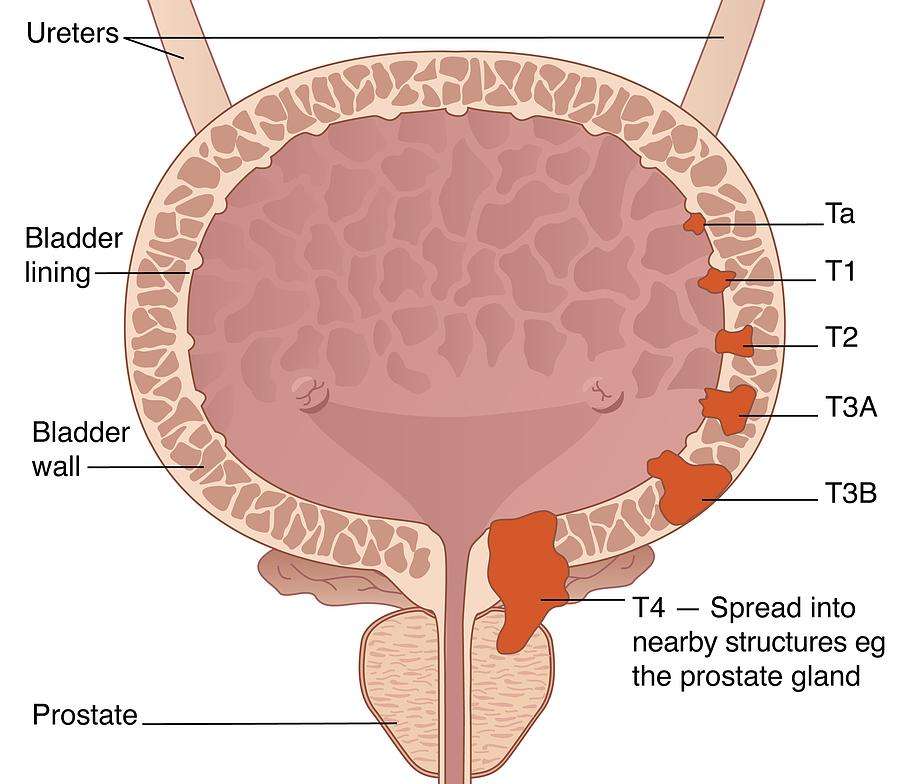

Bladder Cancer Stages And Grades – HealthyBladderClub.com

Staging and grading of bladder cancer – Macmillan Cancer Support

Classification Of Bladder Tumors : TNM stage classification of bladder …

Stages of bladder cancer from Meyer et al., (2002). Bladder cancer can …

Overview of staging and grading of bladder cancer tumor. The figure was …

Bladder cancer stages stock illustration. Illustration of inside – 10332948

Classification Of Bladder Tumors : TNM stage classification of bladder …

Bladder Cancer Staging | MedicineBTG.com